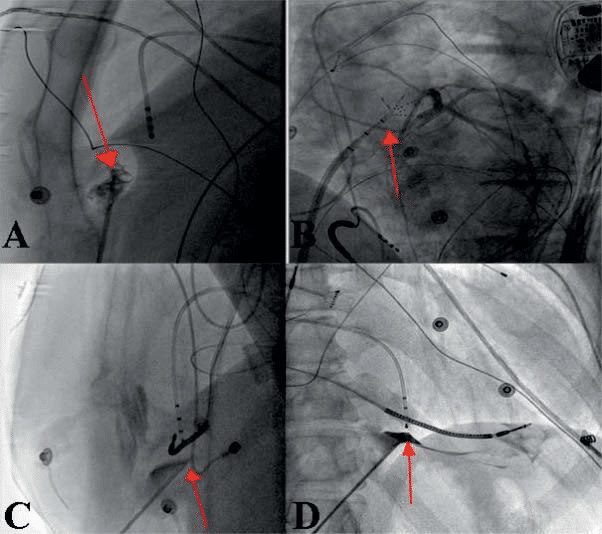

As initially described by Sosa et al. in 199610, the non – surgical percutaneous pericard puncture using a subxyphoidal access became the most utilized pericar-dial access for epicardial ablation of VT. Due to the low associated complications the anteri-or pericardial (Figure 3A, 3B) access became the most used technique and represents the standard approach in our center. Still in some patients, most frequently due to pericardial adhesions, the posterior pericardial puncture represents an alternative but may be associ-ated with a higher complications rate (i.e. accidental liver puncture, injury of posterior interventricular ar-tery) – Figure 3C, 3D. Pericardial adhesions may also be mobilized carefully manipulating the ablation catheter bluntly dissecting adhesions. This technique should only be used in experienced centers and on-site cardio-surgical backup in case of acute epicardial bleeding may be needed. In rare cases (i.e. in patients with history of open heart surgery) a surgical pericardial window may be the only alternative for access into the pericard. The indication for epicardial VT ablation must critically appraise the complications associated with different access routes. Technically the pericardial puncture is usually per-formed using a dedicated non traumatic needle (i.e. Tuhoy needle or micropuncture needle) as described in Figure 3.

Figure 3. Technique of epicardial puncture – 3A – LAO 90° projection: anterior subxyphoidal transcutaneous epicardial puncture – the puncture needle is oriented to the free wall of RV (here also air bubbles in pericard ) with evidence of pericardial adhesions; 3B – LAO 50° projection: epicardial sheath and multipolar mapping catheter also on the anterior surface of RV (red arrow); 3C – LAO 90° projection: posterior epicardial puncture – puncture needle oriented to the inferior LV wall; 3D – RAO 30° – pericard tenting after contrast dye injection preceding the successful pericardial puncture.